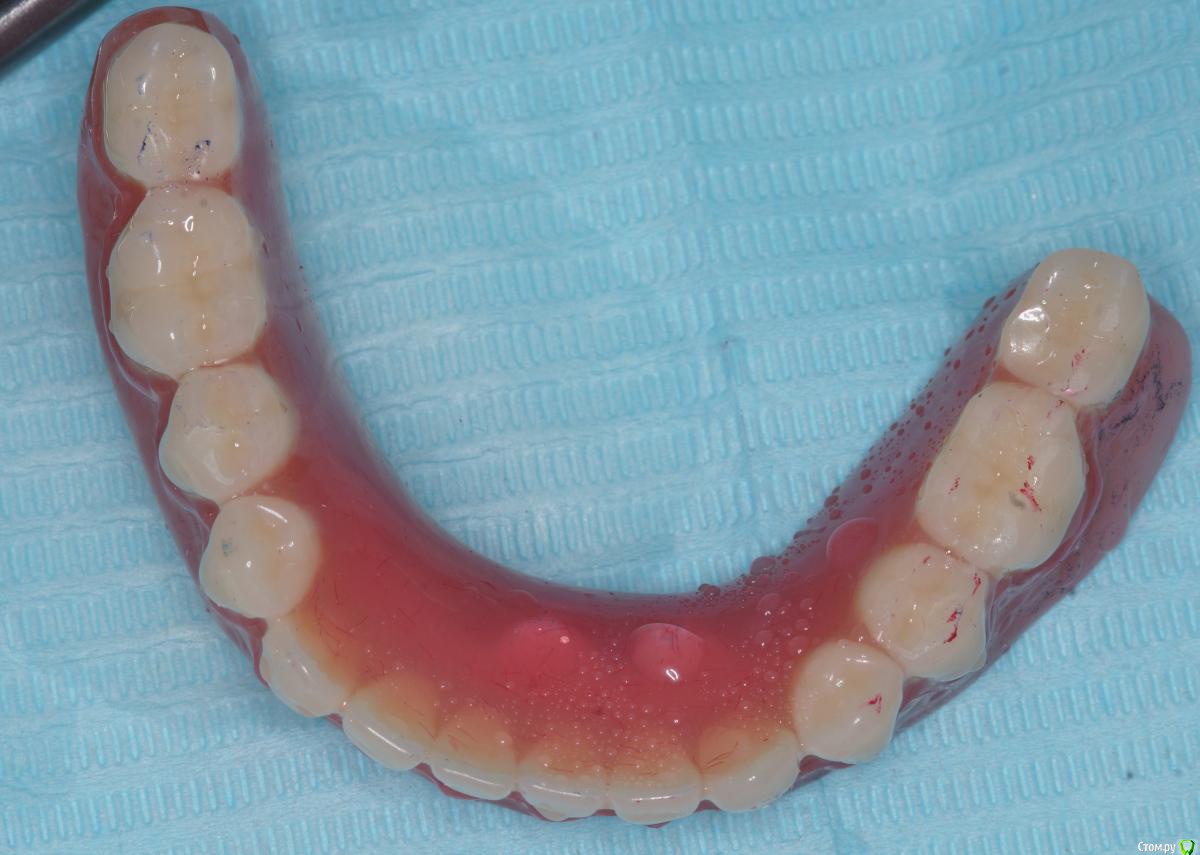

Ответная часть в протезе post-36568-0-74785100-1566455400_thumb.jpg

Сам протез post-36568-0-12150800-1566455435_thumb.jpg